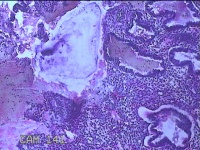

宫腔内容物

性别

女

年龄

42岁

临床诊断

异常子宫出血;贫血

一般病史

阴道流血半个月。

标本名称

大体所见

灰白暗红色不规则碎组织2.3x2x0.8cm一堆。